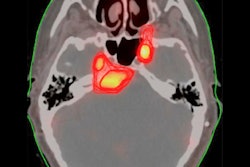

To that end, Canadian researchers recently led an international group proposing a new PET-based framework for tracking longitudinal tau neuropathologic changes, from early to late stages of Alzheimer's disease. The model integrates tau PET data with a gold-standard clinical histopathological staging system -- namely, Braak staging. Read about it here in this edition's Insider Exclusive.

- A group led by Stanford University analyzed tau PET scans and found divergent patterns of cortical tau uptake in 9% of individuals with early Alzheimer's disease.

- Mayo Clinic researchers in Rochester, MN, developed a method called the "overlap index" for tau PET imaging, in which identical voxels showing tau protein deposits can be measured in serial scans over time.